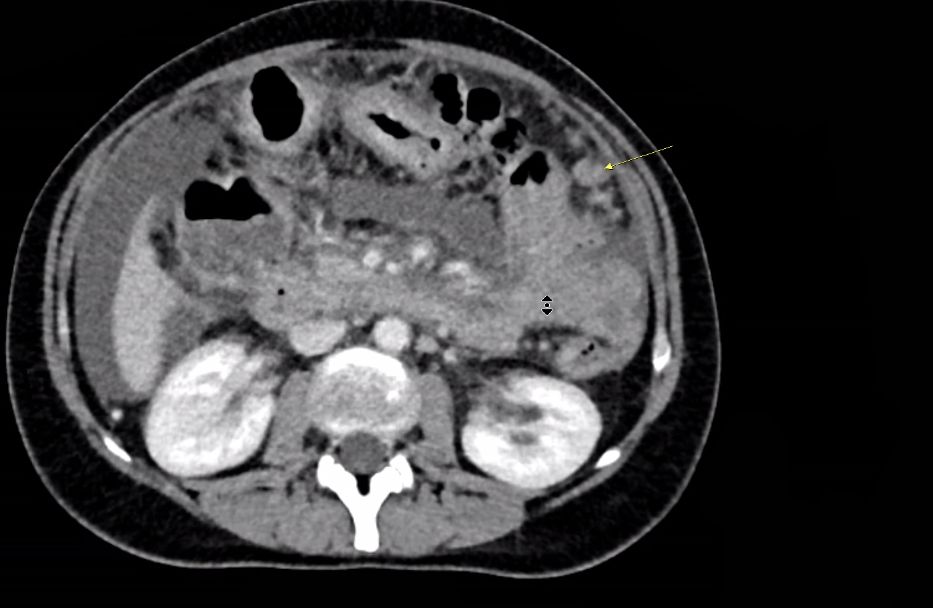

| Peritoneum | 43-jährige Frau mit fortgeschrittenem Magenkarzinom. Knotenveränderungen an der inneren Bauchwand (gelber Pfeil) sprechen für eine Peritonealkarzinose. Links: deutlicher Aszites.![]() | ||